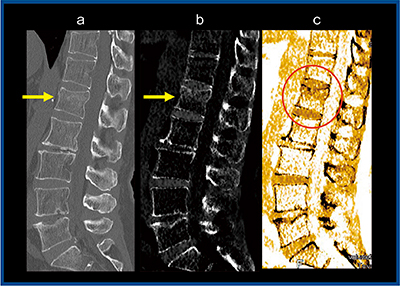

症例4は,腰椎椎体骨折。単純X線写真では骨折を描出できず,135kVpのMPR画像(図4 a→)では第1腰椎の椎体骨折がかろうじて認められるが,BBIでは一見して高吸収域を確認できる(図4 b→,c○)。このことから,先にBBIを見てからMPR画像を観察することで,読影時間の短縮化も可能になると思われる。また,症例5のような多椎体変形の腰椎椎体骨折では,骨折部位の確認が困難であるが,BBIを施行し高吸収域を見ることで,すぐに骨折箇所を同定できる(図5→)。

図5 症例5:腰椎椎体骨折(多椎体変形)

a:MPR画像 b:BBI(グレイスケール画像) c:BBI(カラー画像)

(画像提供:奥州市総合水沢病院・高橋伸光先生)